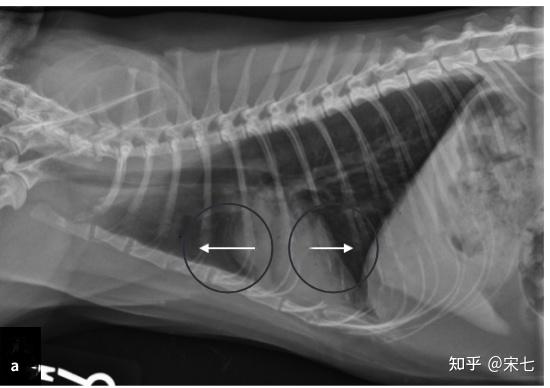

猫传腹(fip)的影像诊断

图片尺寸806x302